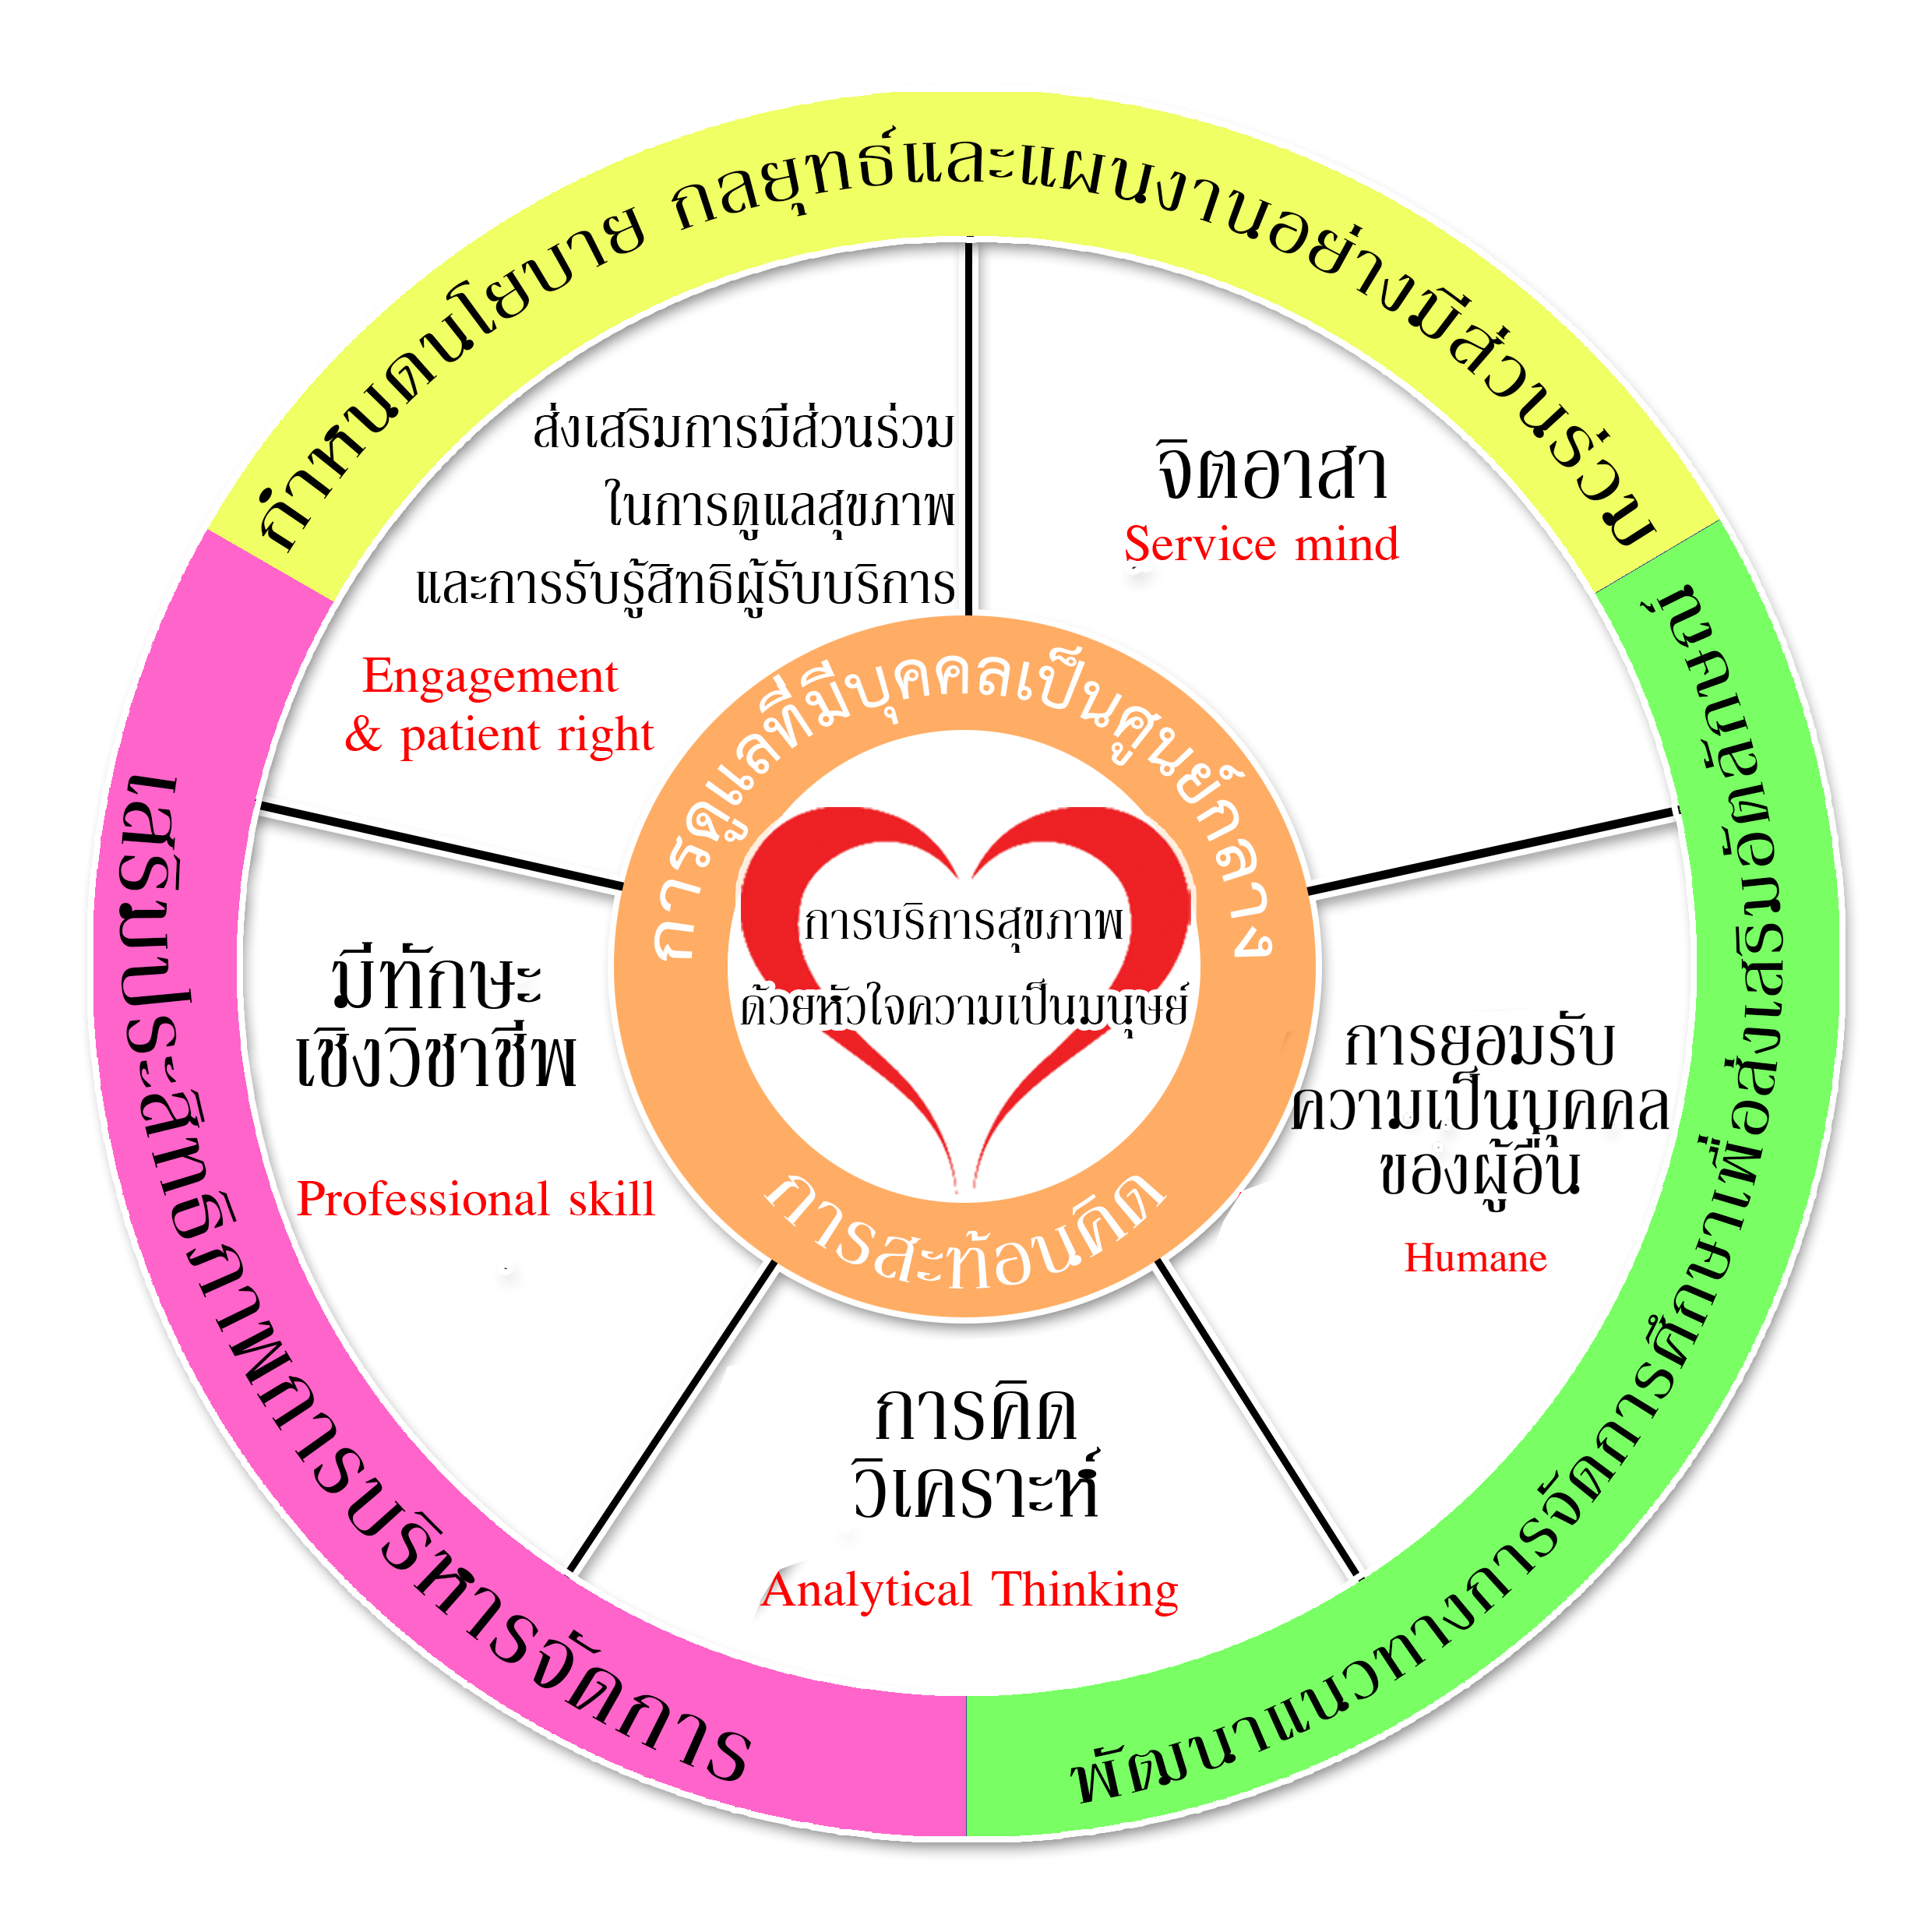

อัตตลักษณ์บัณฑิต ขุนแผนหัวใจมนุษย์ บูชาพระคุณครูบาบุญปั๋น พระล้านนา.คอม เว็บ พระเครื่อง …